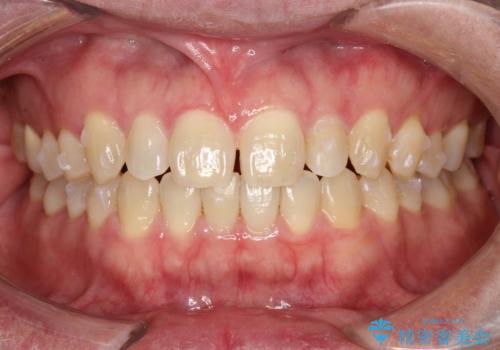

前歯の隙間 インビザラインにて整った歯並びへ

- 前歯の隙間が気になるとのことで来院されました。

インビザラインにて矯正治療を行うこととしました。

下の歯と歯の間にわずかに隙間をつくり、上の前歯の隙間を閉じました。